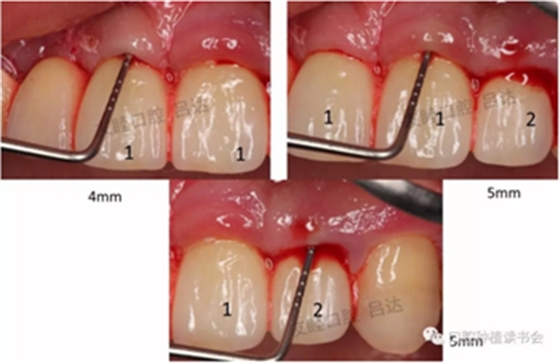

圖2 頰側(cè)探診深度

圖3 舌側(cè)探診深度

檢查可現(xiàn):1|12三個(gè)種植體唇側(cè)粘膜水腫,有探痛,溢膿、出血明顯,探診深度4-5mm。